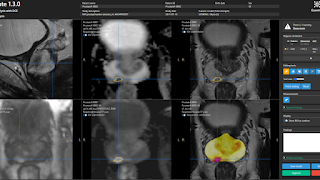

Quantib ontwikkelt en verkoopt software waarmee radiologen snel en accuraat diagnoses kunnen stellen op medische beelden. De software is gestoeld op AI. Zelflerende software dus, die grote hoeveelheden scans verwerkt en daardoor patronen leert te herkennen die klinisch relevant zijn.